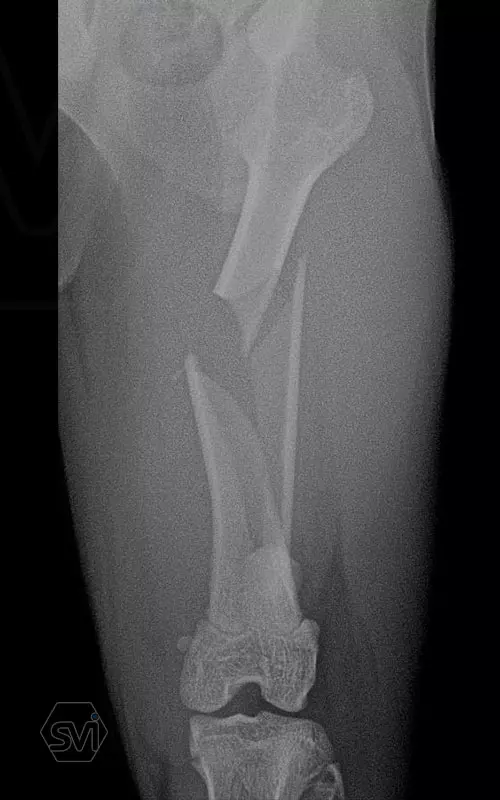

In our case, a middle third fragment fracture of a 10-month-old kitten was treated with a 2.0 polyaxial plate and a combination of 2.0 and 2.4 screws.

Esetünkben egy 10 hónapos cica középső harmadiszilánkos törését kezeltük 2,0 poliaxiális lemezzel és 2,0 és 2,4 csavarok kombinációjával.